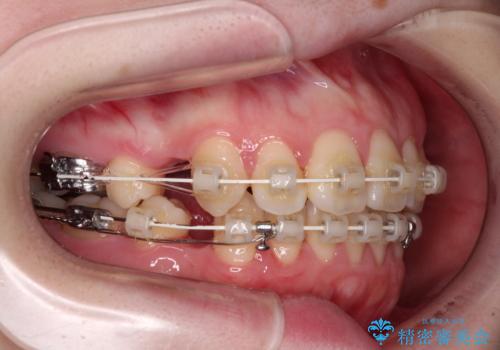

- 審美装置

上顎前歯をしっかりと後方に移動させるため、口蓋側にアンカースクリューと補助装置を併用し、上下左右の第一小臼歯4本を抜歯し、ワイヤー装置にて矯正治療を行うこととしました。

また、舌のトレーニングをしっかりと行うことで、突出癖改善を試みることとしました。